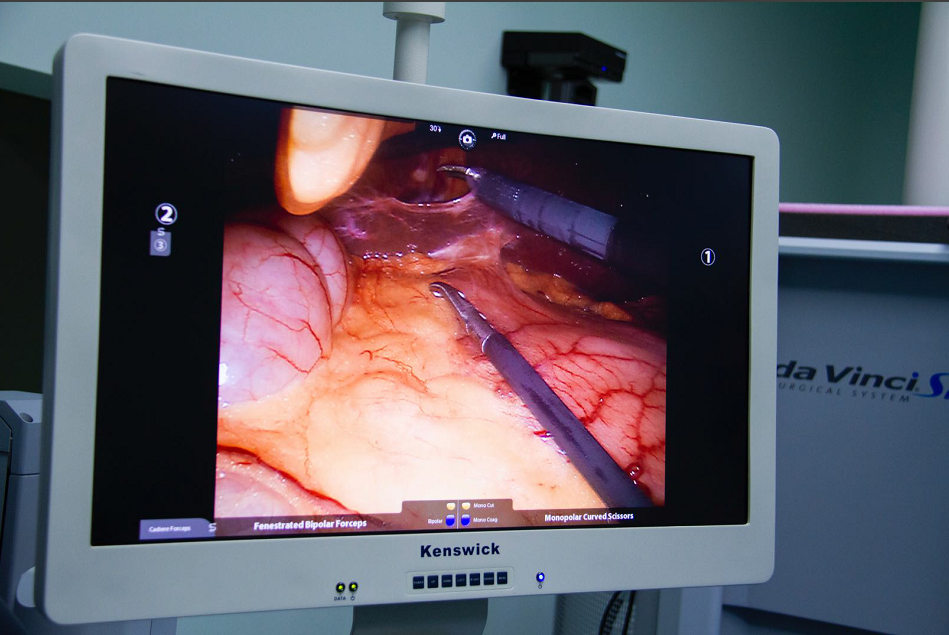

达芬奇手术机器人的全称是内窥镜手术器械控制系统(英文名da Vnici S),它与腹腔镜系统相结合,主刀外科医师在远离手术台的操作控制台,用手遥控着装配在手术台上的4个机械臂,控制连接在机械臂上的腹腔镜和手术器械的动作和运转,完成各类手术。可以说达芬奇手术机器人的出现,将外科医师从手术台上解放了出来。

1、机器人的摄像系统为外科医师提供了更清晰和逼真的三维视野,机器人的“眼睛”高清立体,手术视野放大10倍,细小的组织也难逃火眼金睛;

光学放大10倍的高清晰立体图像